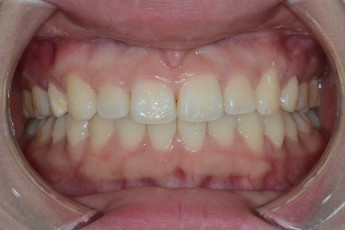

BEFORE & AFTER